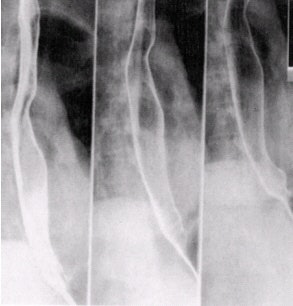

![]() |

| Single-contrast study of esophagus in RAO position with table top in head-down -20° position. Image courtesy of Dr. Naveed Ahmad. |